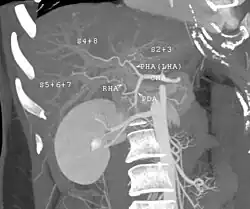

| Trauma abdominal resultando em uma contusão no rim direito (seta aberta) e sangue ao redor do rim (seta fechada), conforme visto em tomografia computadorizada. | |

Os rins também podem ser lesionados; eles são parcialmente, mas não completamente, protegidos pelas costelas.[6] Lacerações e contusões renais também podem ocorrer.[11] Lesões renais, um achado comum em crianças com trauma abdominal contuso, podem estar associadas a sangue na urina.[10] Lacerações renais podem estar associadas a urinoma ou vazamento de urina para o abdômen.[4] Um rim fragmentado é aquele com múltiplas lacerações e uma fragmentação associada do tecido renal.[4]